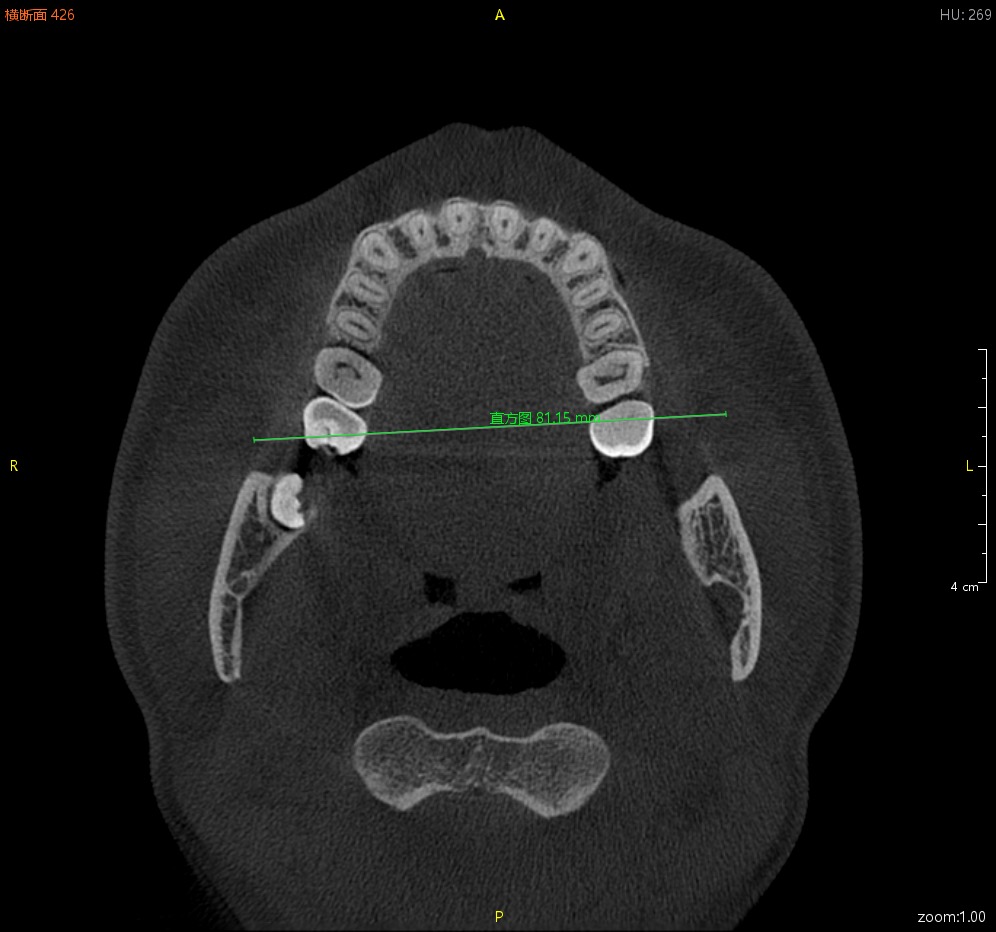

方便实用的测量工具

直线测量、曲线测量、折线测量、角度测量、区域面积测量以及骨密度测量

直线测量 折线测量 曲线测量 角度测量 区域测量 骨密度测量 箭头与注释工具

直线测量